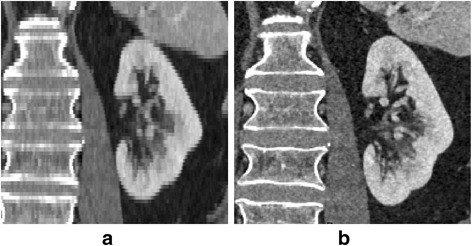

As scan and reconstruction parameters directly affect image quality, imaging protocols need to be optimized to meet the needs of 3D modeling. For example, lower tube potential (kV) can be used in CT to increase the enhancement of iodine contrast when building vascular models [24]. Contrast injection and bolus timing can be adjusted to separate arterial and venous phases of the contrast enhancement. Image slice thickness and reconstruction kernel are important factors influencing the spatial resolution and image noise. Thick images can generate discontinuous, stair-step like boundaries on the segmented model (Fig. 1). The reconstruction kernel impacts both spatial resolution and image noise, which need to be balanced based on particular applications. For models with fine structures, such as the temporal bone, a sharp kernel is more appropriate to get the best spatial resolution (Fig. 2). Conversely, for models with moderate to large size, low contrast objects, such as liver lesions, a smooth kernel is more appropriate to control image noise (Fig. 2).

Fig. 1.

a kidney model made off 3 mm slice thickness showed stairwell artifacts, while they were not visible on the model made off 0.6 mm slice thickness (b)

Fig. 2.

Temporal bone (a, b) and liver (c, d) images reconstructed with soft (a, c) and sharp kernels (b, d)